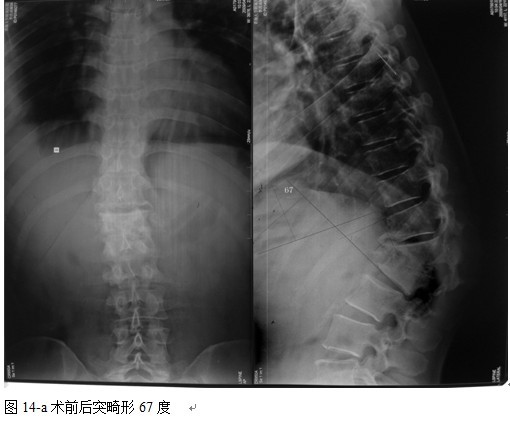

中国学者金大地[22]等采用一期前路病灶清除植骨前路钢板固定治疗腰椎结核,平均18°的后凸畸形得以矫正,Mukhtar[23] AM等采用前路病灶清除植骨分期或同期后路固定治疗腰椎结核22例,术后后凸畸形矫正度数平均为27°。从我们的随访结果看,术后后凸畸形平均矫正度数为26.9°,后凸畸形平均矫正90%以上, 6个月-49个月后随访,后凸角度平均丢失4.2°。本术式也适用于结核所引起的弹性差的后凸畸形,对于病灶纤维化或骨化的非弹性后凸畸形,后路固定后,先行前路病灶、纤维化或骨化切除、松解,逐步刮除病灶、逐步撑开,达到畸形矫正和植骨的目的。

结果: 术后所有患者均显示,骨性融合, 马尾神经损伤的患者均基本恢复正常,术后后凸畸形平均矫正90%以上, 3-49个月的随访,后凸角度平均丢失4.2°。